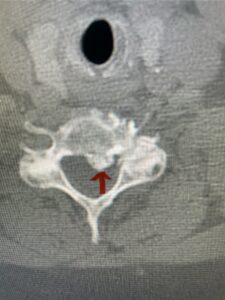

This 61-year-old female with a history of severe osteoporosis and a prior history of a laminectomy from l2-S1 with an L5-S1 instrumented fusion, presents with progressive low back pain and right lower extremity radiculopathy. MRI revealed a grade 1 L2-3 spondylolisthesis with severe stenosis mainly from severe right L2-3 facet joint hypertrophy which was compressing the right L3 descending nerve root. (Fig. 1). She had failed conservative management consisting of physical therapy and pain management with epidurals. She underwent an L1-3 revision laminectomy where we had to dissect a plane underneath the inferior aspect of the L2 lamina. We performed an instrumented fusion at L2-3 with special hydroxyapatite-coated screws to improve fixation to surrounding bone given here severe osteoporosis (Fig. 2) This worked out well and the patient had an uneventful recovery with relief of her leg pain.

Figures 1a: Sagittal and axial T2-weighted lumbar MRIs demonstrating a grade 1 L2-3 spondylolisthesis (red arrow) with severe stenosis secondary to right L2-3 facet hypertrophy (red arrow).

Fig 1b: Note the left L2-3 facet joint (blue arrow) is normal in size compared to the right (red arrow)